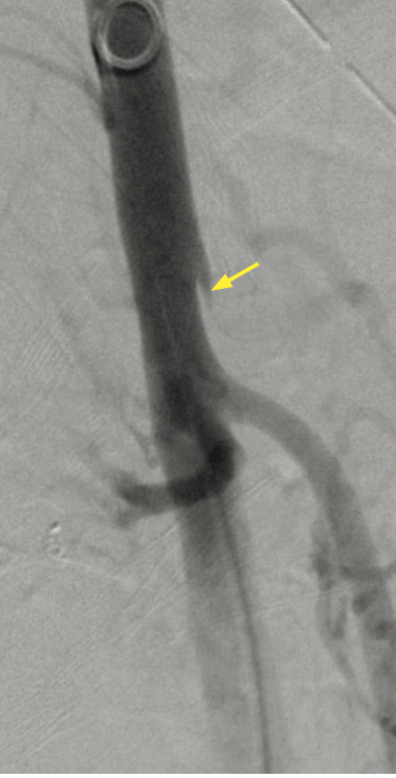

• Celiac Artery compression by the median arcuate ligament

• Post-stenotic dilatation of celiac artery

• Look for “hook” / “J” sign